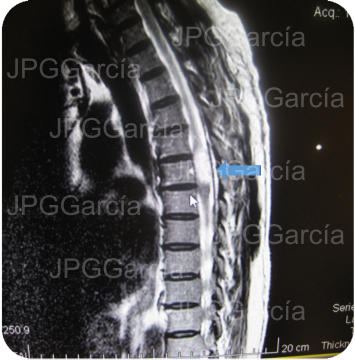

Estudio de resonancia magnética prequirúrgico que demuestra

una lesión tumoral torácica relacionada a un meningioma

RESECCIÓN MICROQUIRÚRGICA DE MENINGIOMA TORÁCICO

Estudio de resonancia magnética prequirúrgico que demuestra una lesión tumoral torácica relacionada a un meningioma